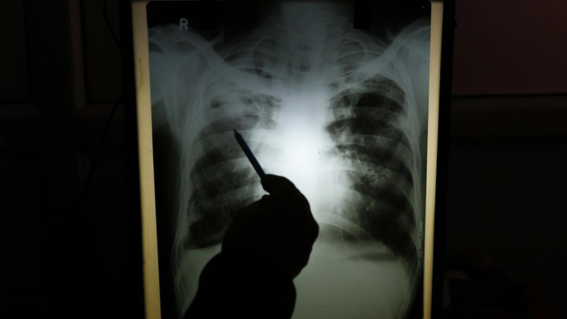

24 मार्च 2026 (भारत बानी ब्यूरो ) : भारत में दवा प्रतिरोधी ट्यूबरकुलोसिस (DR-TB) तेजी से एक गंभीर स्वास्थ्य संकट बनता जा रहा है। यह बीमारी सामान्य टीबी की तुलना में अधिक खतरनाक और इलाज में जटिल होती है। स्वास्थ्य विशेषज्ञों का कहना है कि यदि इसे समय रहते नियंत्रित नहीं किया गया, तो यह राष्ट्रीय स्तर पर स्वास्थ्य आपातकाल की स्थिति पैदा कर सकती है।

दवा प्रतिरोधी टीबी उन रोगियों में होती है जो पारंपरिक एंटी-टीबी दवाओं से ठीक नहीं हो पाते। अक्सर मरीजों द्वारा दवाओं का समय पर सेवन न करना या दवाओं की कमी, गलत डोज़, या अधूरा इलाज इसका कारण बनता है। भारत में टीबी की दर सबसे अधिक है, और इस बीच DR-TB मामलों में लगातार बढ़ोतरी देखी जा रही है।

हाल के आंकड़ों के अनुसार, भारत में हर साल लगभग 1.5 लाख से अधिक DR-TB के मामले सामने आते हैं। विश्व स्वास्थ्य संगठन (WHO) ने इसे वैश्विक चिंता का विषय बताया है, और भारत सरकार ने भी इसे स्वास्थ्य नीति में प्राथमिकता देने की बात कही है। विशेषज्ञों का मानना है कि अगर उपचार और रोकथाम पर तत्काल कदम नहीं उठाए गए, तो यह स्थिति गंभीर हो सकती है।